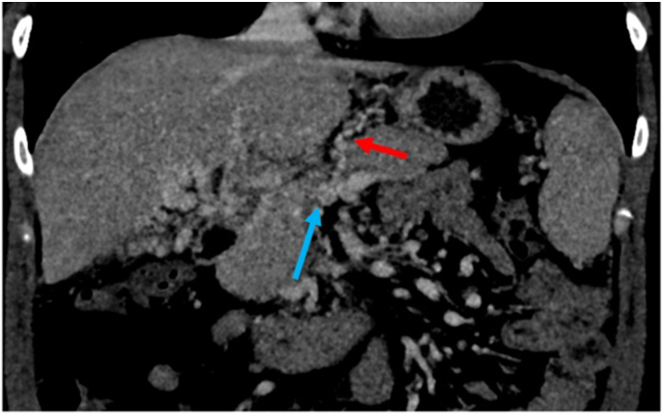

门静脉再通经颈静脉肝内门静脉系统分流术(pvrtips)是一种安全有效的门静脉高压症(PH)减压手术。在这个简短的病例系列中,2名患有慢性非肝硬化门静脉血栓的女性接受了PVR-TIPS治疗。两个病人都希望怀孕。如果不治疗她们的PH值,她们的怀孕会造成危及生命的静脉曲张出血的重大风险。两名患者对手术耐受良好,分娩时没有出现PH并发症。在未来希望怀孕的非肝硬化门静脉血栓患者中,PVR-TIPS应被考虑作为PH的最终治疗。

Portal vein recanalization transjugular intrahepatic portosystemic shunt (PVR-TIPS) is a safe and effective procedure for decompression of portal hypertension (PH). In this short case series, 2 women with chronic noncirrhotic portal vein thrombosis were treated with PVR-TIPS. Both patients hoped to conceive. Without treatment for their PH, their pregnancies posed a significant risk of life-threatening variceal bleeding. Both patients tolerated the procedure well and delivered without complications of PH. In future cases of noncirrhotic portal vein thrombosis in patients hoping to conceive, PVR-TIPS should be considered for definitive treatment of PH.